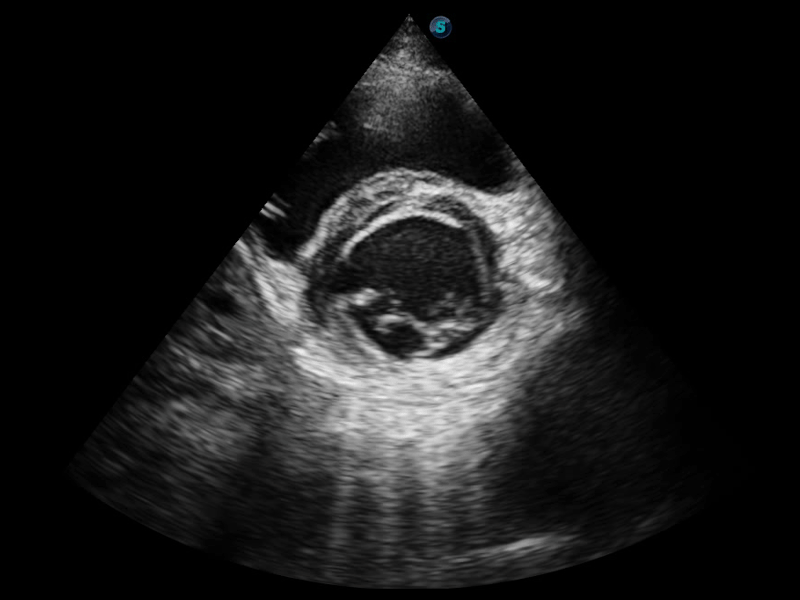

S-Live 高分辨率容积成像

通过仿真成像技术对3D/4D立体数据进行渲染,多种初始光源位置可选,并支持轨迹球360°光源位置自由调节,清晰显示不同方位容积图像细节。